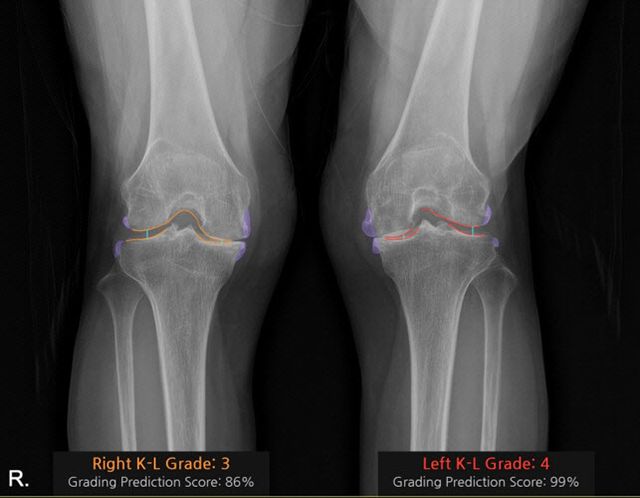

‘코네보 코아(CONNEVO KOA)’는 무릎 X-ray 영상을 분석해 관절염 심각도를 ‘K-L(Kellgren-Lawrence) 등급’으로 판정하고, 골극과 관절 간격을 시각화해 제공한다. 이를 통해 진단의 일관성을 높이고 환자와 상담 시 유용한 시각자료로 활용할 수 있다.

공동 연구자인 중앙대병원 정형외과 김성환 교수는 “AI 솔루션이 관절염 상태를 직관적으로 보여줘 환자 이해도가 크게 향상됐다”며 “실제 사용 경험에서도 만족도가 매우 높다”고 말했다.